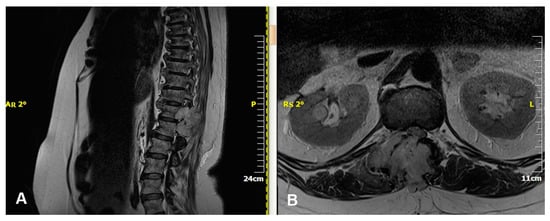

3.4. Diagnostic Evaluation